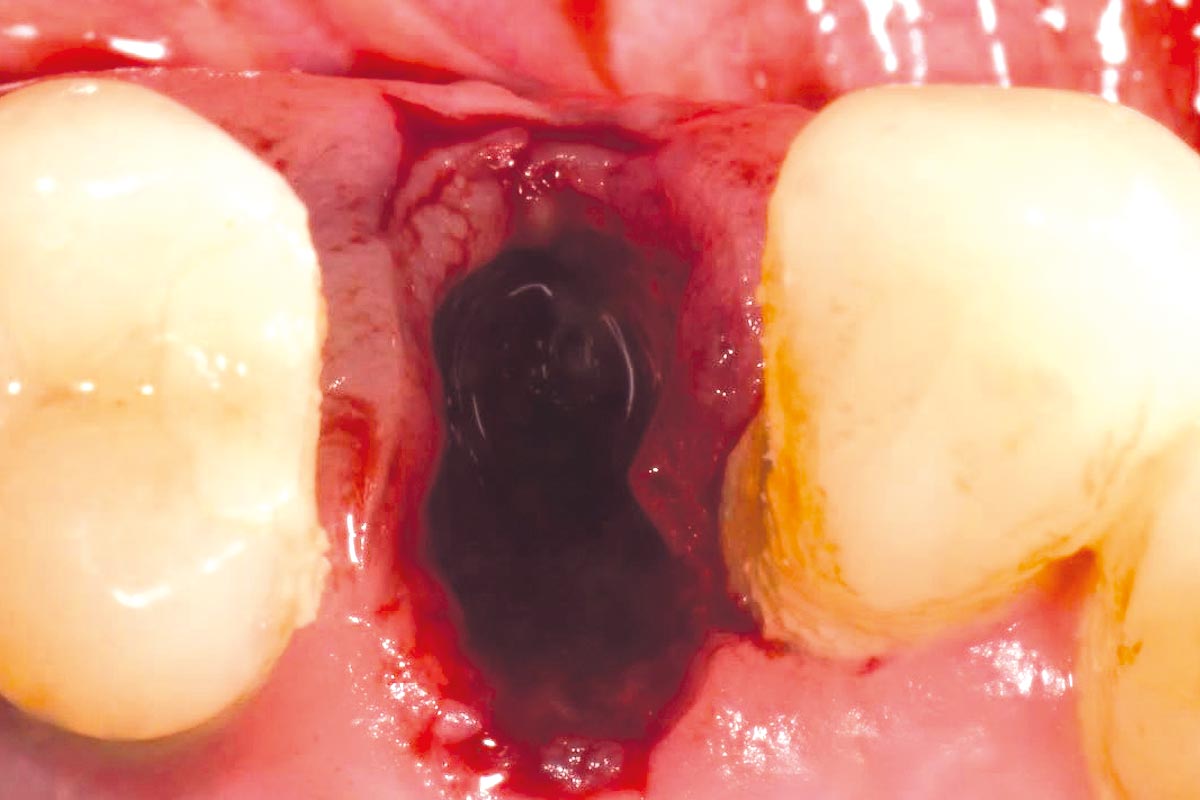

In this case, the initial socket preservation was performed using suboptimal biomaterials, resulting in insufficient bone regeneration. A preoperative CBCT assessment was conducted to evaluate the socket condition and surrounding bone structure.

At the six-month re-entry, insufficient regeneration of the buccal plate was observed, compromising the available bone volume for implant placement. To address this deficiency, NOVAMag® SHIELD was introduced to reconstruct the buccal plate. Thus, an implant was placed followed by a membrane placement between the periosteum and the remaining buccal bone without fixation. Additional bone augmentation was performed to facilitate guided bone regeneration.